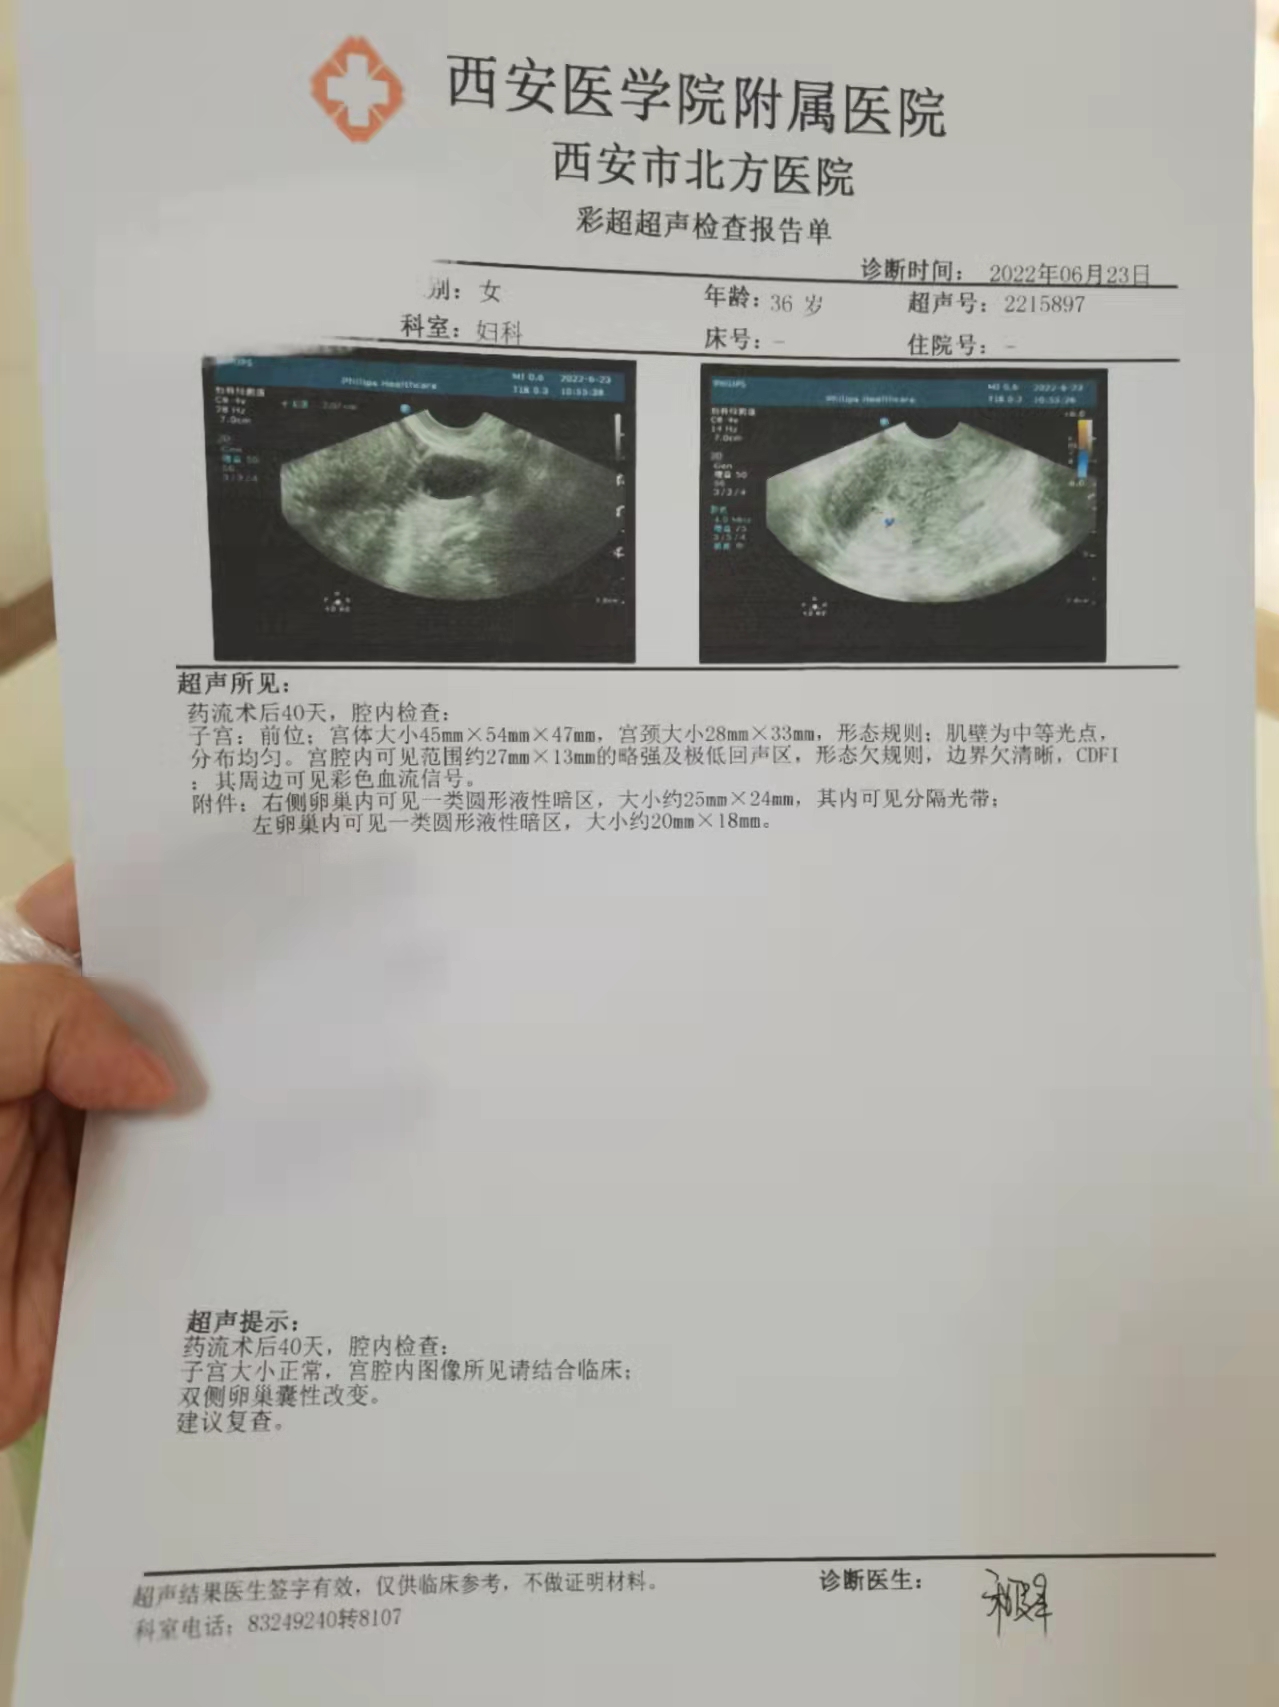

西安医学院第二附属医院对患者造成误诊

图片尺寸1279x1707